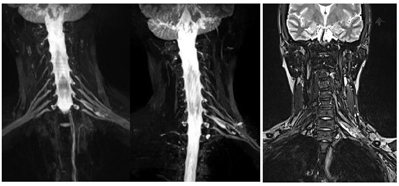

术后查体:左肘腕关节活动自如,左臂屈曲、外展可,神经感觉未见明显异常。术后肿瘤组织送病理检查,HE染色示神经鞘瘤。免疫组化结果:S100(+),SMA(-)。术后2周后未出现臂丛神经损伤症状及其他并发症,治愈出院。术后1周(图3)、1个月(图4)、半年(图5)、一年(图6)复查颈部MRI+增强及臂丛神经重建如下。